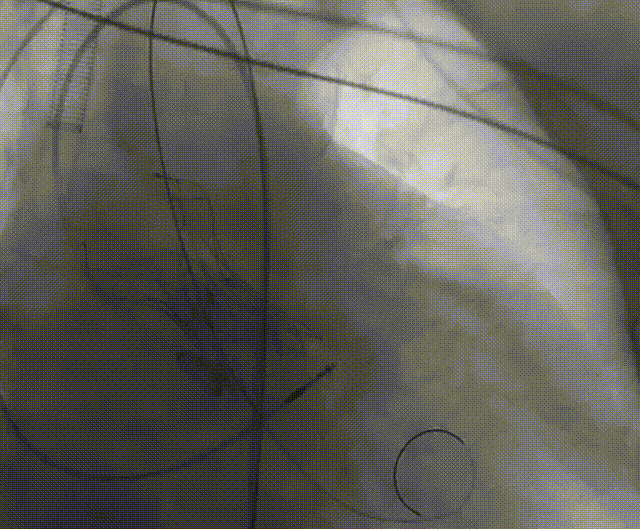

手术流程概括

22球囊扩张,无明显腰增,无造影剂泄露。

瓣膜初始零位释放,释放后位置尚可,决定完全释放。

瓣膜释放后有瓣周漏显示决定进行球囊后扩。

后扩后形态良好,瓣膜展开充分,轻微瓣周漏。